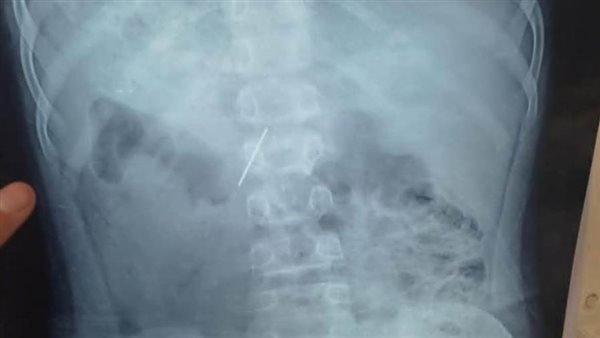

نجح قسم جراحة الأطفال بمستشفى الأطفال التخصصي ببنها، في استخراج مسمار دباسة كراسة اخترق جدار بطن طفل واستقر داخل التجويف البطني، بعد تدخّل جراحي متقدّم جمع بين المنظار الجراحي وجهاز السي أرم لتحديد الموقع بدقة متناهية.

وصل الطفل إلى المستشفى وهو يعاني ألمًا شديدًا وقلقًا أسرته، وكشفت الفحوصات الأولية وجود جسم غريب حاد داخل البطن. قرار الفريق كان حاسمًا، استئصال المسمار بأسرع وآمن طريقة ممكنة لتفادي أي مضاعفات قد تهدد حياة المريض.

قاد العملية فريق متميز بقيادة الدكتور محمد متولى رئيس قسم جراحة الأطفال، وبمشاركة د. وليد محمد استشاري جراحة الأطفال ود. محمود ممدوح نائب قسم جراحة الأطفال، تم توظيف المنظار الجراحي لتقليل آثار الجراحة والشفاء السريع، فيما لعب جهاز السي أرم دور الخريطة الحية لتحديد موقع المسمار بدقة مدهشة، ما حول العملية إلى مزيج من مهارة الجراح وذكاء الأجهزة.